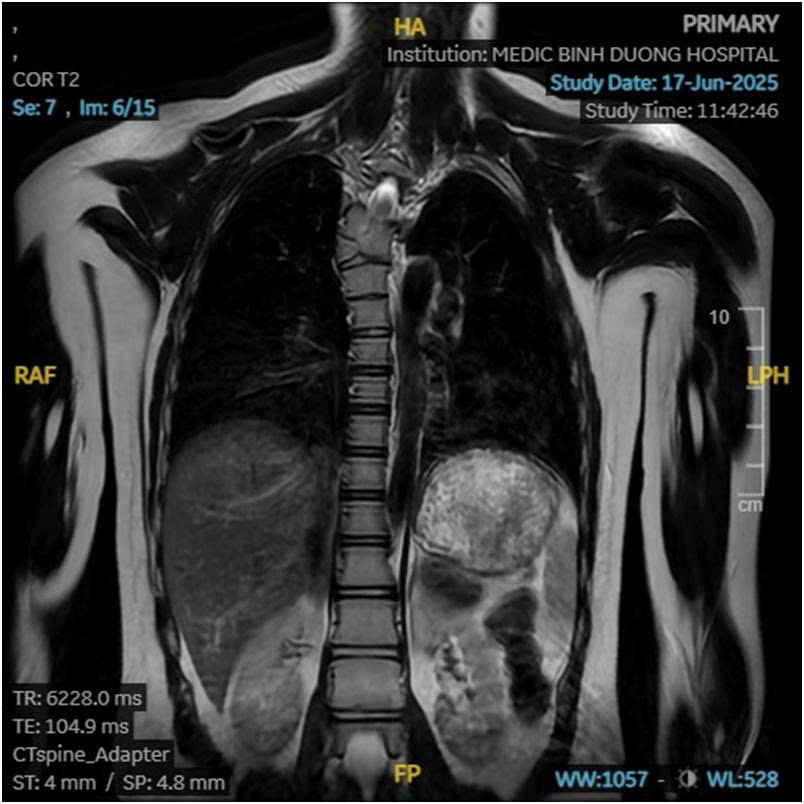

Hình1: Dị tât đốt sống ngực bán phần ở tầng T6 gây vẹo cột sống.

Sau bao ngày trăn trở và tìm kiếm, một cuộc thăm khám tại bệnh viện Medic Bình Dương đã hé lộ nguyên nhân thực sự: đó là vẹo cột sống do một dị tật bẩm sinh hiếm gặp mang tên Đốt sống bán phần ( Hemivertebra) ở cột sống ngực.

Cột sống của chúng ta được cấu tạo từ nhiều đốt xương nhỏ xếp chồng lên nhau. Ở người bình thường, mỗi đốt sống có hình dạng khối đều đặn. Tuy nhiên, ở những người mắc đốt sống bán phần, một phần của đốt sống không phát triển hoàn chỉnh ngay từ khi còn trong bụng mẹ. Điều này khiến đốt sống có hình dạng như một cái nêm, làm cho cột sống không còn thẳng mà bị cong vẹo. Đây thường là nguyên nhân chính gây ra vẹo cột sống bẩm sinh, hoặc đôi khi là gù (cong ra sau) hay ưỡn (cong ra trước).